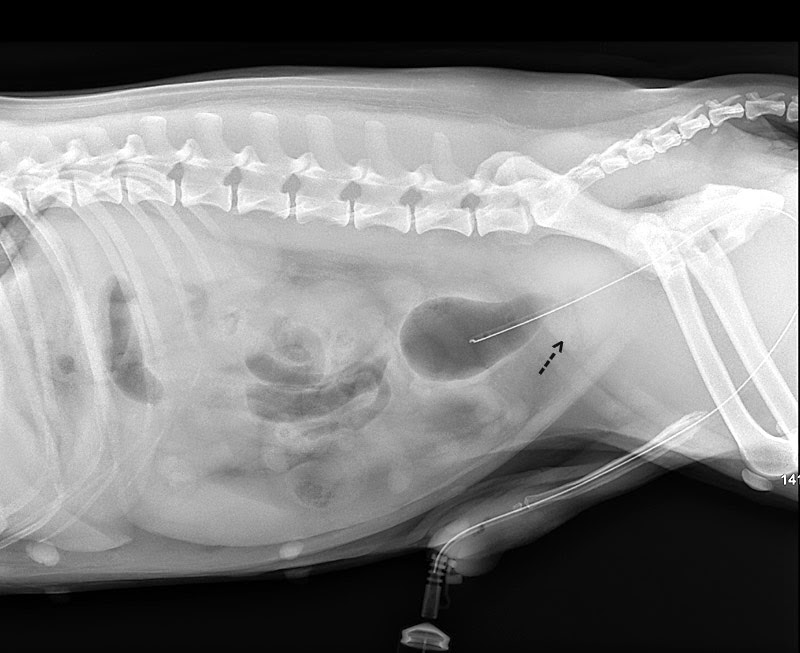

X RAYS

Bacterial prostatitis or prostate abscess

| Bladder infection |

20 ml air was pumped into the bladder to check for bladder stones and to define the thickness of the wall of the bladder. This was a case of urinary tract infection. After Baytril antibiotics, the dog could control his bladder the 2nd day. Neuter was advised.